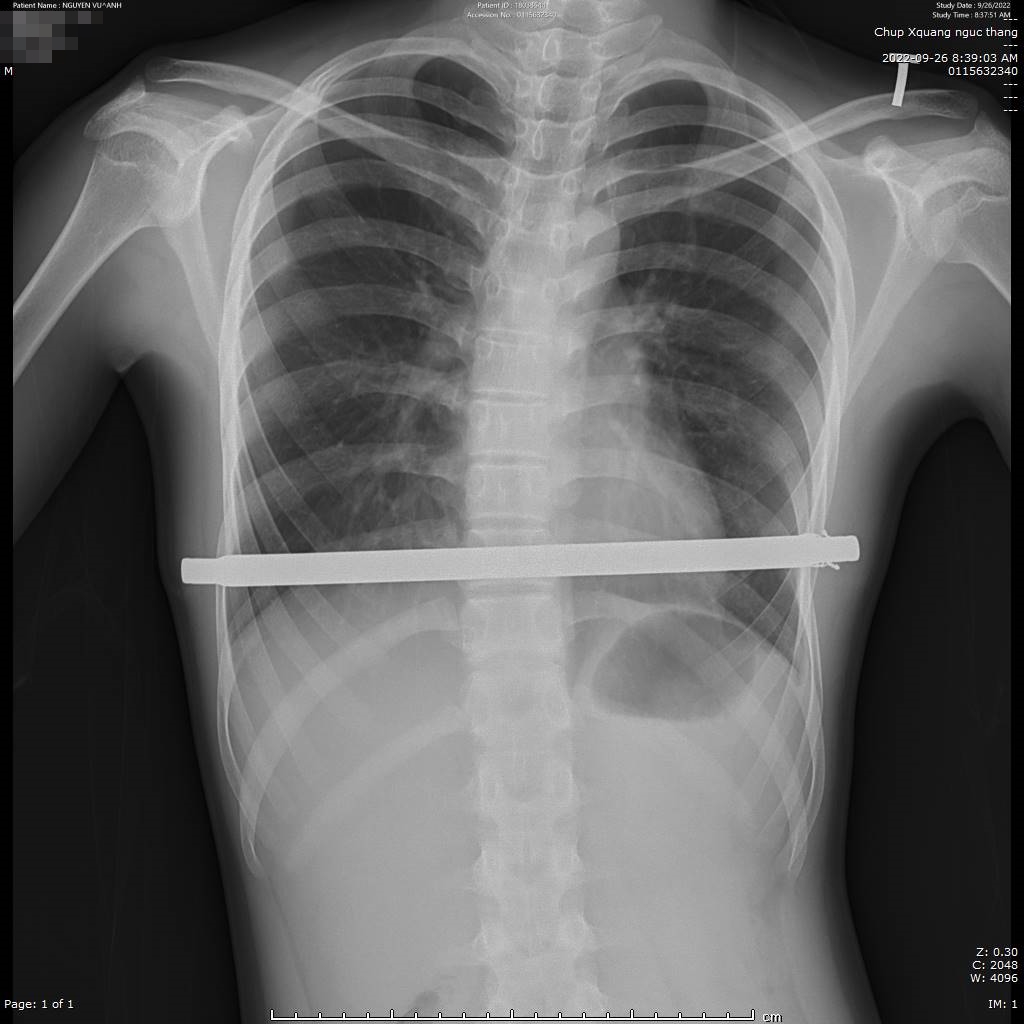

Hình ảnh chụp x-quang thanh nâng ngực.

Ca mổ được thực hiện bởi đội ngũ bác sĩ khoa ngoại có tay nghề, kinh nghiệm trong phẫu thuật lồng ngực phối hợp với khoa gây mê hồi sức. Phẫu thuật viên tiến hành rạch hai đường ngắn (khoảng 2cm) ở dọc khoang liên sườn hai bên. Dưới hướng dẫn của hệ thống nội soi 3D, bác sĩ khéo léo tạo đường hầm sau xương ức, sau đó luồn một thanh kim loại cứng được uốn cong phù hợp với hình dạng ngực để làm giá đỡ nâng vùng xương ức bị lõm lên vị trí xác định. Thanh kim loại này có tác dụng nâng khối xương lên, giải phóng lồng ngực về đúng vị trí và định hướng cho khối xương phát triển bình thường mà không bị lõm vào trong. Ca phẫu thuật diễn ra nhanh chóng, thuận lợi trong 45 phút thực hiện. Sau phẫu thuật nội soi đặt thanh nâng chỉnh hình, lồng ngực bệnh nhi nở rộng bình thường, sức khỏe phục hồi tốt và xuất viện trong thời gian ngắn.